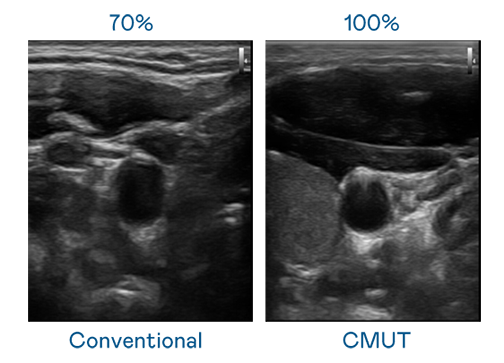

CMUT 技术是一种用电容式微机电元件来产生超音波讯号的技术。与传统 PZT 压电式技术相比,CMUT 频宽增加 30%,更宽频的超音波讯号让影像解析度大幅提升,是实现高影像品质医疗超音波扫描、促进精准医疗发展的关键技术。

超音波影像的解析度高低,首先取决于探头能发出的讯号频宽。威斯尼斯wns888 CMUT 可提供高清晰的超音波讯号,提供高频宽、高灵敏度、影像纹理细节更高的超音波影像,协助医护人员缩短影像判读时间及利用精准的医疗影像进行诊断。